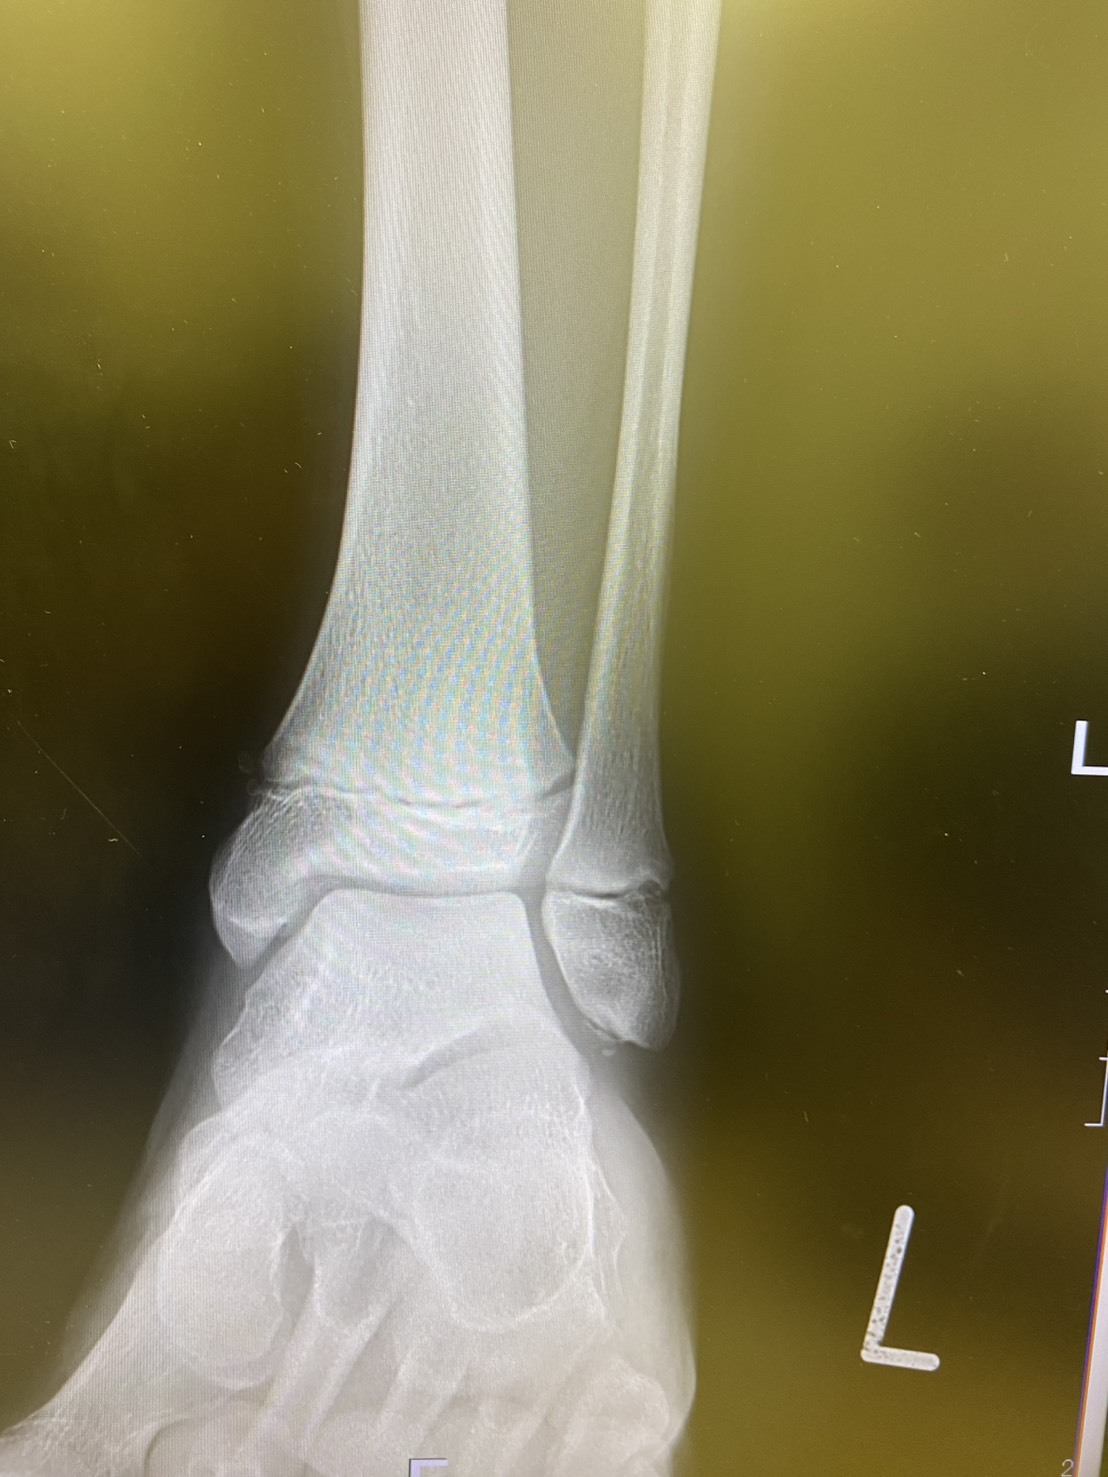

- バレーで足を踏み左足を負傷